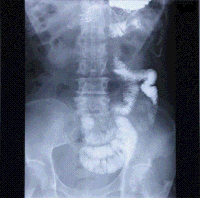

【消化管透視撮影(DR)】

透視装置で撮影された画像データはすべてデジタル保管され、ネットワークPCで見ることができます。また過去の画像と比べてみたり、白黒反転やフィルターをかけたりして読影医師の好みに応じ画像表示することができます。

平成22年3月にCアーム搭載オールデジタルX線テレビ(フラットパネル)に更新しました。